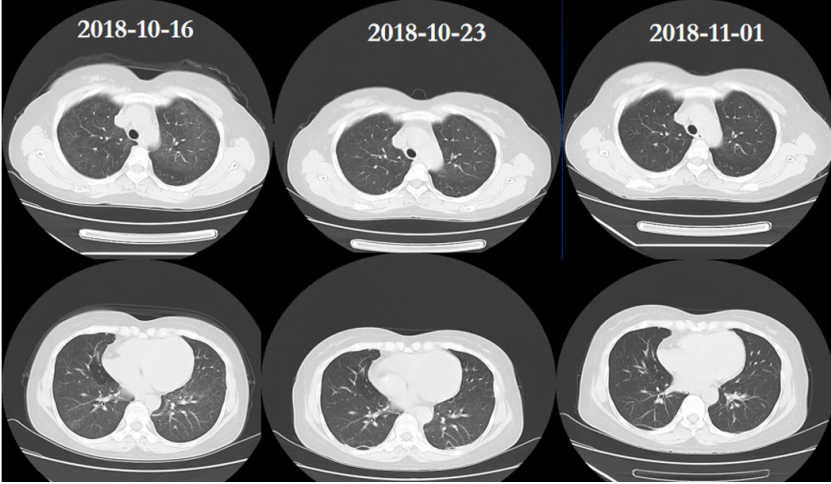

1CMV肺炎:单纯的CMV肺炎比较罕见,笔者中心1000多例移植患者仅有2例发生CMV肺炎。其中1例患者肾移植术后1月余,发热1天。影像学可见双肺弥漫性病变,多发结节(图12)CMV肺炎进展及恢复速度都很快(图13)

13  患者治疗前后胸部CT变化

2)排异:肾移植术后2年,胸闷半月。双肺弥漫性渗出(图14)BALF分类计数:中性粒细胞占4.9%,嗜酸性粒细胞占17.1%,淋巴细胞占45.8%,组织细胞占20.1%,纤毛柱状上皮细胞占12%,未见肿瘤细胞及真菌感染依据。吉姆萨染色、PAS和PASM染色均阴性。患者BALF细胞计数以淋巴细胞及嗜酸性粒细胞为主,往往提示非感染性炎症,肾脏科会诊考虑为排异,予甲泼尼龙治疗后快速好转(图15)

15  甲泼尼龙治疗前后胸部CT对比